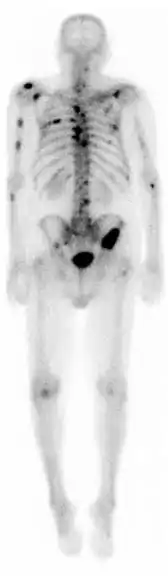

![]() A nuclear medicine whole-body bone scan. The nuclear medicine whole-body bone scan is generally used in evaluations of various bone-related pathology, such as for bone pain, stress fracture, nonmalignant bone lesions, bone infections, or the spread of cancer to the bone. | |